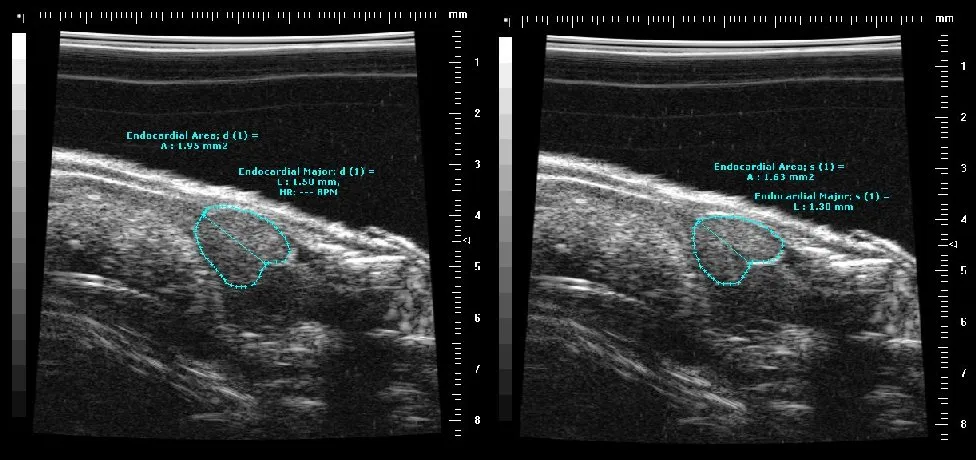

Zebrafish

ultrasound image of adult fish heart

End systolic and end diastolic length and area measurements of an adult zebrafish heart